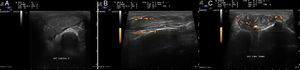

Paciente varón de 85 años con antecedentes de HTA, dislipemia, cardiopatía isquémica, con angor inestable revascularizado en 1985 mediante doble bypass coronario. Tratamiento habitual con: amlodipino, atorvastatina, pentoxifilina, telmisartán/hidroclorotiazida, omeprazol, tramadol y AAS. Acude a reumatología por sospecha de artritis severa de la muñeca derecha, sin antecedente traumático (fig. 1A). La exploración pone de manifiesto una masa de partes blandas en el receso medio-cubital, tumefacta, dolorosa a la palpación, desplazable, en ausencia de fiebre, adenopatías o alteración del estado general. Se solicita Rx de manos bilateral que confirma osteopenia difusa, pérdida de la interlínea articular carpiana, medio carpiana y erosión del cúbito distal, de su estiloides, así como calcificaciones vasculares generalizadas (fig. 1B).

A) Imagen de la muñeca derecha del paciente. Tumoración blanda, depresible, desplazable a nivel cubital. B) Radiología simple de manos bilateral. Osteopenia generalizada, disminución de la interlínea articular en la muñeca derecha. Engrosamiento de partes blandas más evidente a nivel de la estiloides cubital. Severa distorsión de la arquitectura de la articulación radio-carpiana y a nivel del receso cubito carpiano.